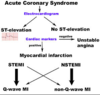

What disorders are included in acute coronary syndrome?

- Unstable angina

- MI: STEMI or NSTEMI

Why does acute coronary syndrome occur?

Atheromatous plaque ruptures and thrombus forms causing an acute increased occlusion and potential infarction

How do you distinguish between UA, NSTEMI and a STEMI?

- ECG’s

- Blood tests

What are the different classifications of MI’s?